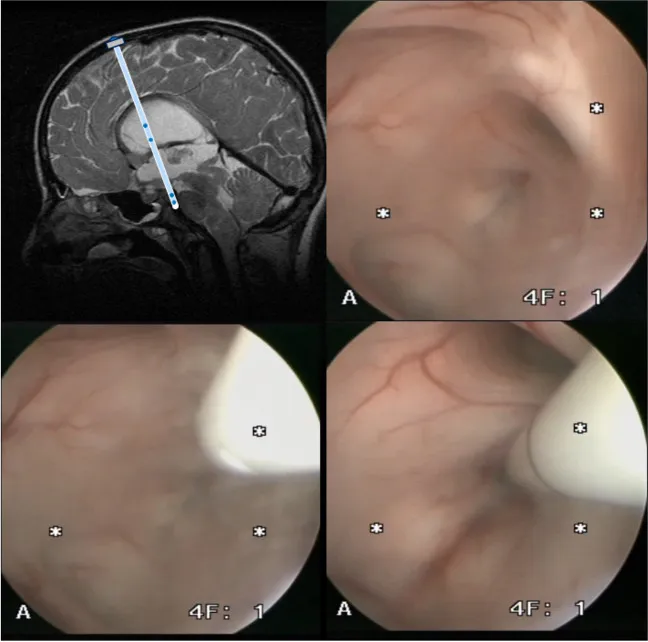

完成标准ETV手术操作后,在平行于内镜的方向上,将一根带有更多近端侧孔的分流管近端导管向前方推进。一旦导管进入侧脑室区域,在直视下将导管经ETV造瘘口推进,使其能够顺利穿过结节体组织,并将导管头端精确放置在蛛网膜下腔区域。随后撤出内镜设备,将导管锚定于硬脑膜组织或Ommaya储液囊。

支架辅助ETV技术需要精确的手术规划甚至需要使用神经导航系统,以便将骨孔定位在与桥前池轨迹、基底动脉、第三脑室底及室间孔最佳对齐的位置。手术目标是将导管头端精确放置在桥前池区域,在导管头端开设侧孔,同时在侧脑室水平段也开设多个侧孔。在内镜直视下,可以清晰观察第三脑室底的具体解剖结构。如果解剖结构因肿瘤等病变发生扭曲变形,需要使用神经导航系统来确定进入桥前池的精确穿刺点。导管沿内镜工作通道平行导入。在内镜视野控制下,将导管头端经第三脑室底置入桥前池区域,置入深度通常约为2.5厘米。